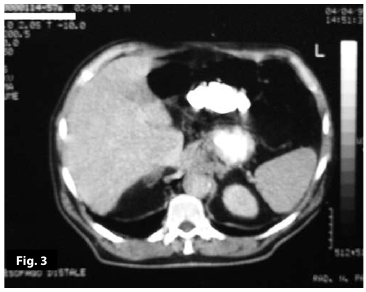

Figure3

Figure3-4